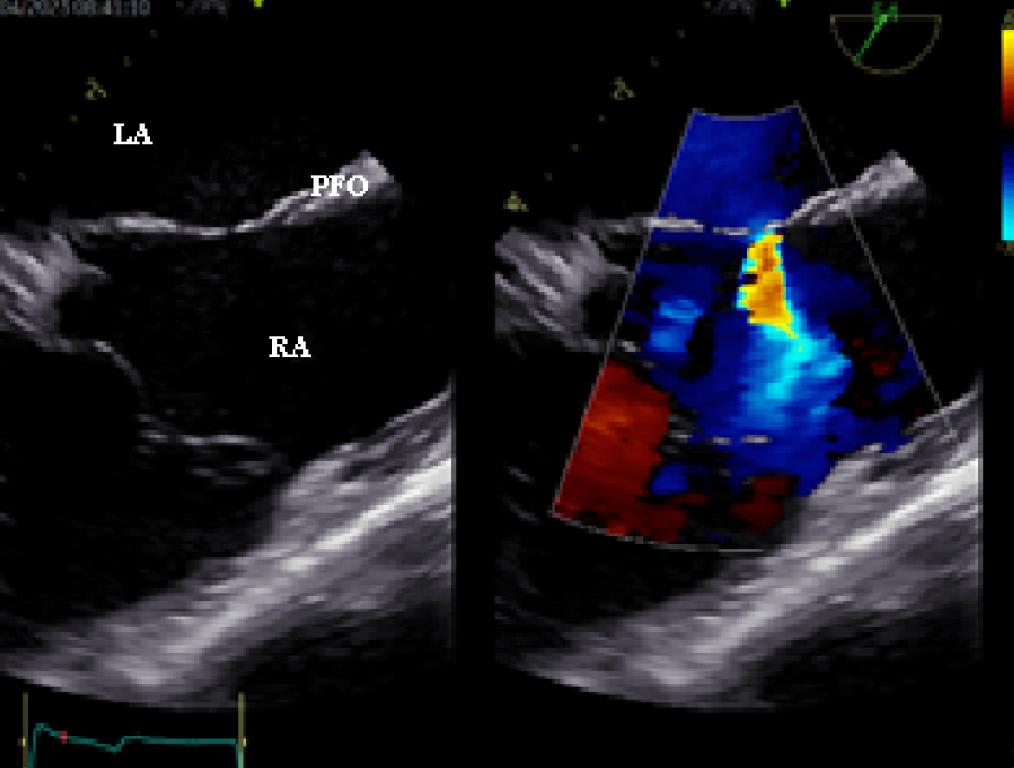

Figure 4